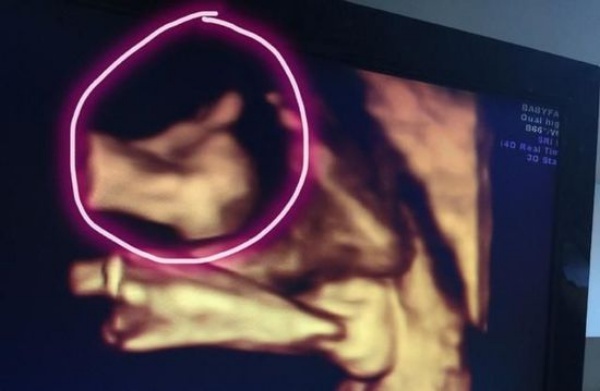

Theo Nam Đô, vào tối 10/10, Lâm Chí Dĩnh chia sẻ ảnh siêu âm hai con trai trên trang cá nhân. Anh chú thích: “Vừa siêu âm hình ảnh 4D, hai em trai lớn hơn rồi, thật là đáng yêu!”. Nhiều người gửi lời chúc phúc đến tài tử Thiên long bát bộ khi sắp sửa lên chức cha lần nữa.

| Phim siêu âm 4D của hai nhóc tì sắp chào đời nhà Lâm Chí Dĩnh. |